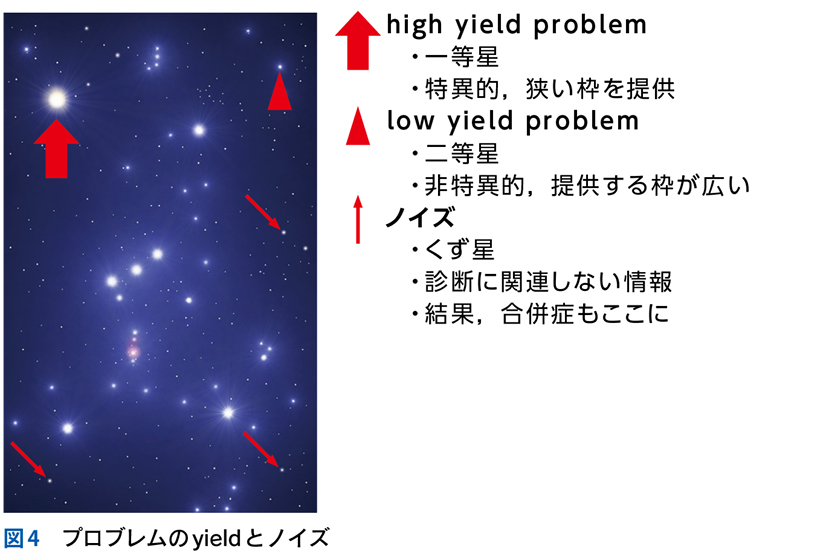

▶ 個々のプロブレムのyieldを,星座を構成する星にたとえれば,high yieldなプロブレムとは一等星である(図4)。その星があるというだけで,可能性のある星座の数が絞られる。low yieldなプロブレムは,星座を構成する二等星以下の星だ。その星(だけ)に注目しても,構成可能な星座の数が多すぎてあまり役には立たない(ただし,二等星以下の星も後述する「順位づけ」では活躍するし,オリオン座の三ツ星のように,二等星以下の星の「組み合わせ」が有力な1つの問題;症候群を形成し,一等星相当になることもある)。

▶ 「ノイズ」は,筆者的には臨床推論においてきわめて重要な概念であるため,第4章で詳述するが,フレーミングに関わるのでここで簡単に紹介しよう。ここでは「ノイズ」を,「患者の持つ情報のうち診断と直接的には関連しないもの」を指す語として使用する。対義語(診断と関連する情報)は「シグナル」である。星座のたとえで言えば「シグナル」は星座を構成する星,「ノイズ」は星座を構成しないが近傍にある「くず星」を指す(図4)。